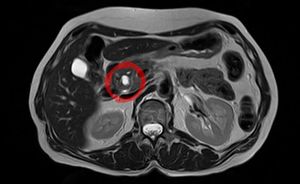

| ورم مخاطي حليمي داخل قناة الپنكرياس يظهر في تصوير بالرنين المغناطيسي. | |

ورم مخاطي حليمي داخل قناة الپنكرياس (Intraductal papillary mucinous neoplasm؛ IPMN) هو نوع من الأورام التي يمكن أن تحدث داخل خلايا قناة الپنكرياس. تُنتج هذه النوعية من الأورام مخاطاً،[1] وهذا المخاط يمكن أن يشكـِّل كيسات پنكرياسية.[2] وبالرغم من أن الأورام المخاطية الحليمية داخل قناة البنكرياس هي أورام حميدة، فيمكنهم أن يتطوروا إلى سرطان الپنكرياس.[1] ولذلك يُنظر إلى IPMN على أنها ورم محتمل الخباثة.[3] وبمجرد أن يـُعثر على ورم مخاطي حليمي داخل قناة البنكرياس، فإن خيارات الإدارة تتضمن المراقبة اللصيقة والجراحة الوقائية.[بحاجة للاستشهاد الطبي]